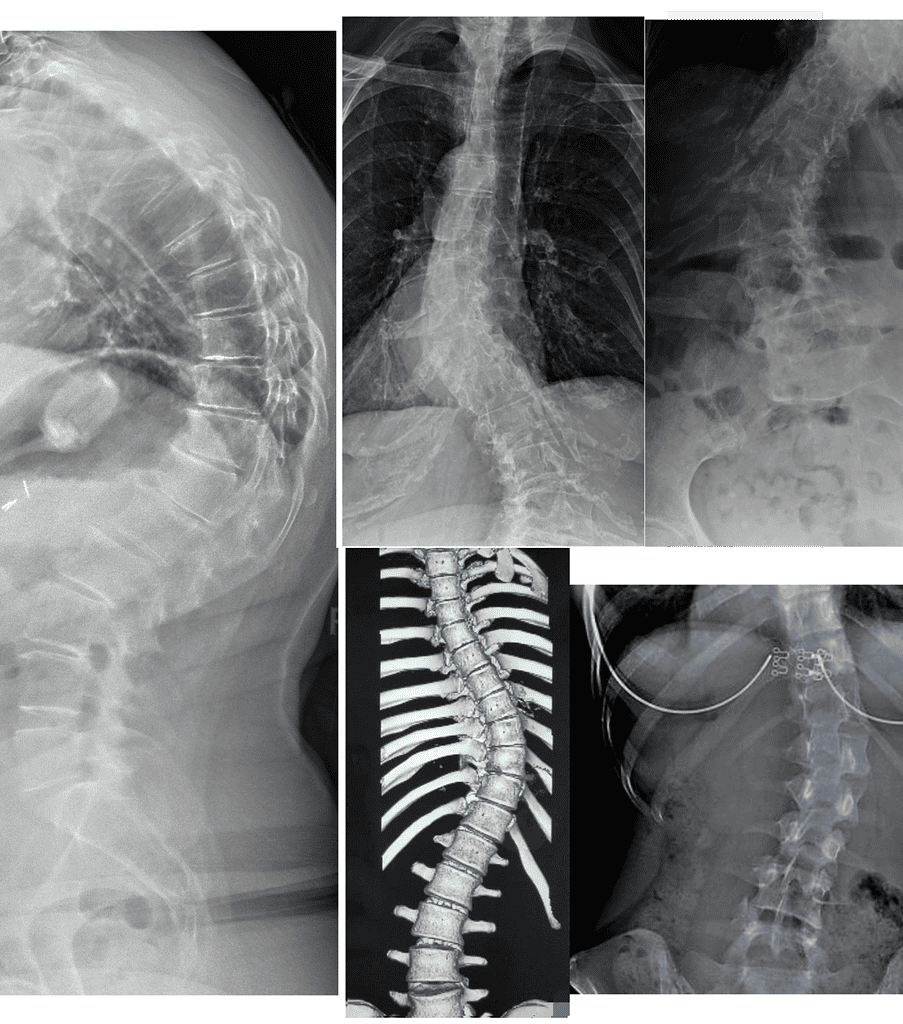

Measurable outcomes on X-ray. Here is what our co-managed patients have experienced.

Note: Individual results vary. All measurements taken on calibrated standing AP radiographs by the treating doctor. Cases shown with patient/guardian consent.

In-Brace Correction is normally 48% but we could see 63%.*

Out-of-Brace curves achieved 37.60% improvement if their curves are 20°-40°.

Results: curve correction: 76.9%, curve stabilization: 23.1%, curve progression 0%